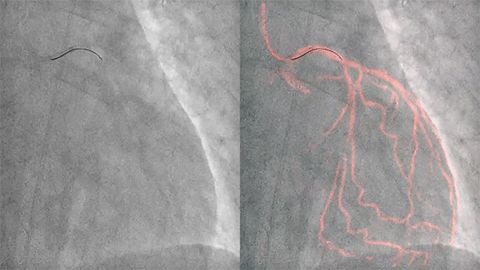

Philips IntraSight interventional platform offers clinically proven5-9 imaging, physiology and co-registration4 tools with unique iFR and FFR features. iFR is the leading hyperemia-free physiologic index for measuring pressure in diagnostic and interventional procedures. Only offered by Philips, iFR is an evidence-based methodology that improves outcomes, saves time, and reduces patient discomfort.5-7 iFR Co-registration4 maps the physiologic measurements directly onto the angiogram enabling more complete procedural guidance.

StentBoost Live offers instantaneous enhanced live visualization to position and deploy balloons, stents and other devices during PCI procedures. Our exclusive Dynamic Coronary Roadmap helps you navigate tortuous coronary arteries efficiently and precisely.

The Azurion integrated cath lab offers IntraSight’s exclusive plug-and-play digital IVUS at table side. The ADAPT-DES study reported that IVUS guidance was associated with a change in PCI strategy 74% of the time.10-13 Our exclusive IVUS Co-registration4 feature maps the 3D vessel anatomy to the angiogram, creating an overlay image which may help you determine lesion significance, vessel sizing and optimal stent deployment for improved treatment outcomes.10,11,14